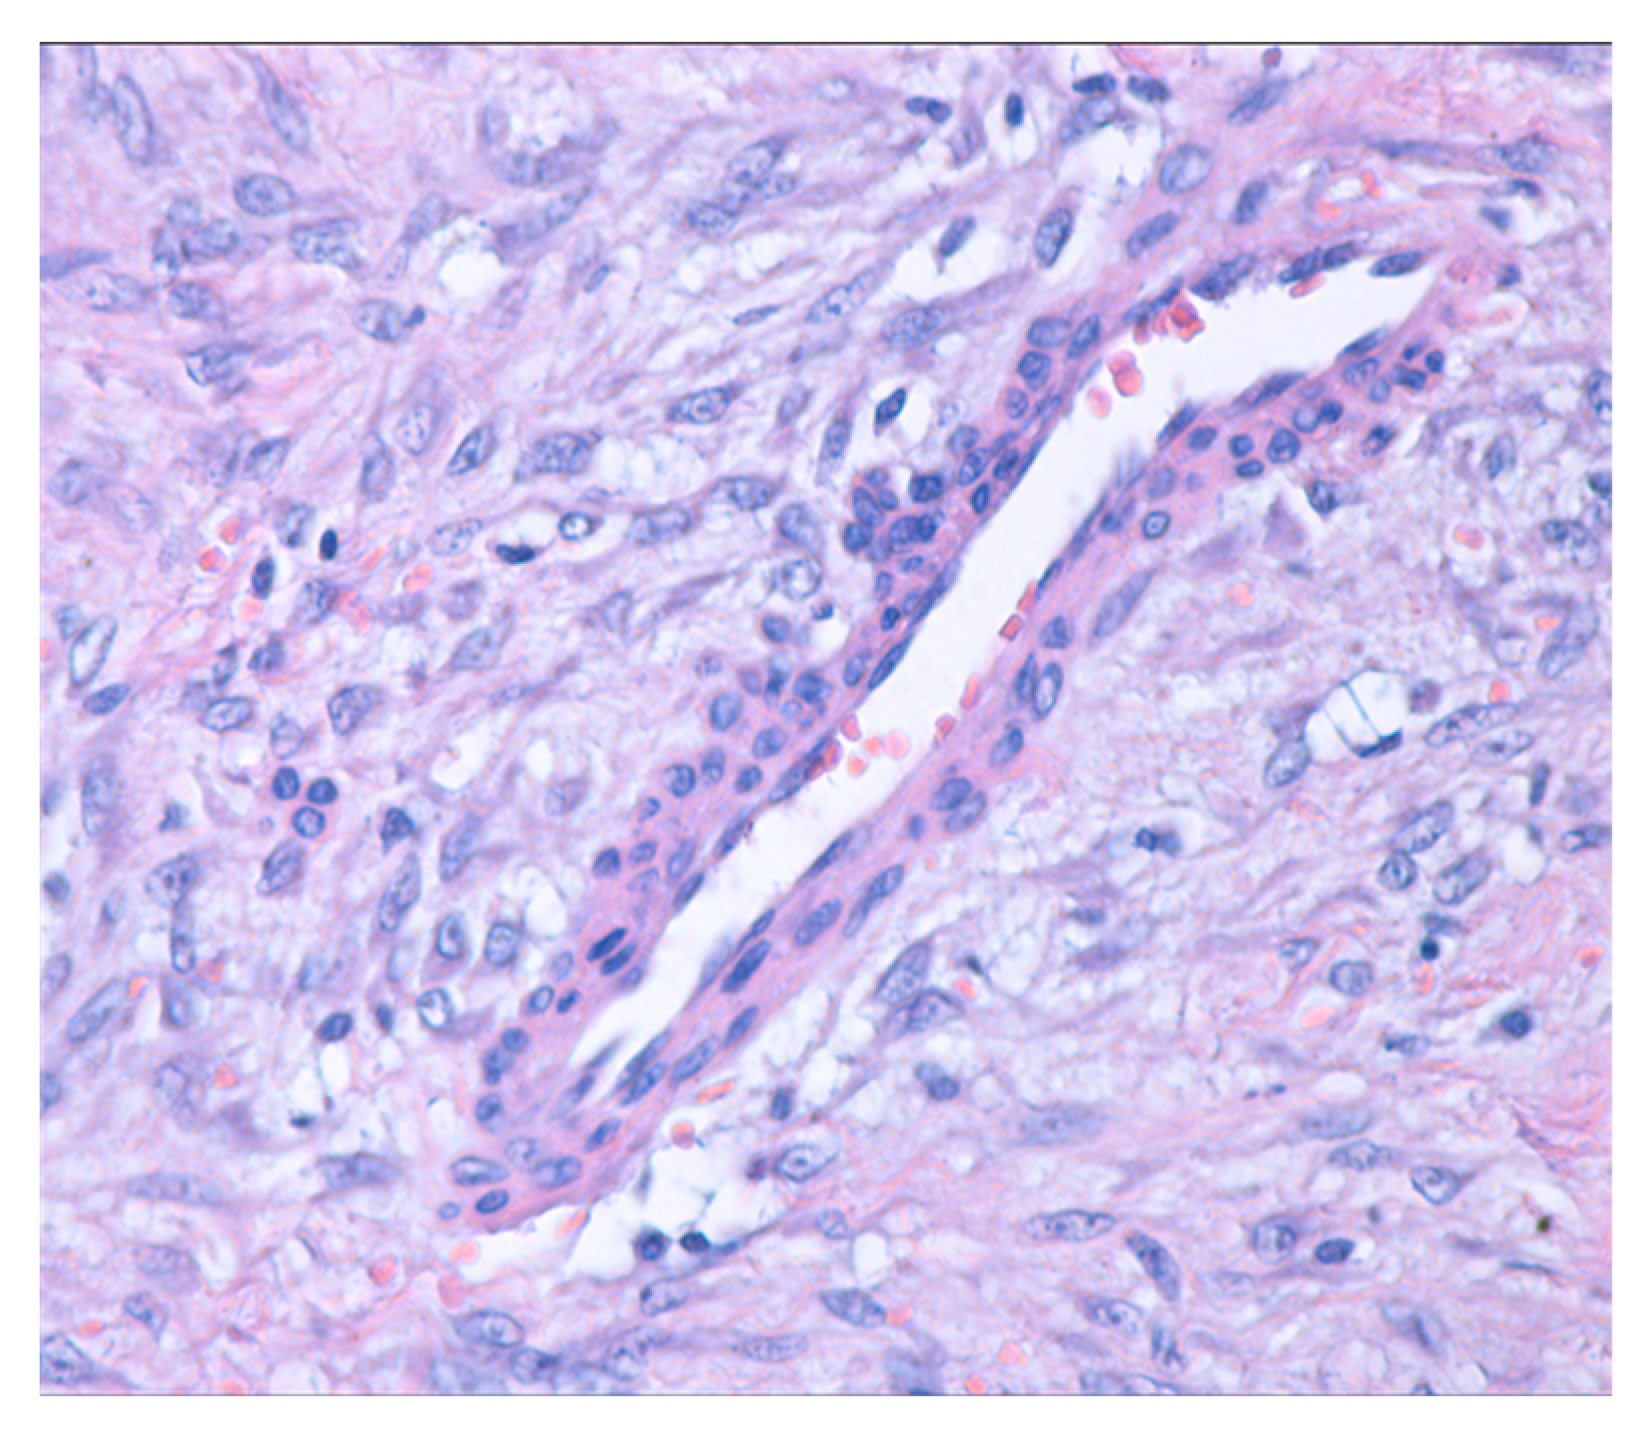

4.3. Histopathological Diagnosis

4.4. Pathology